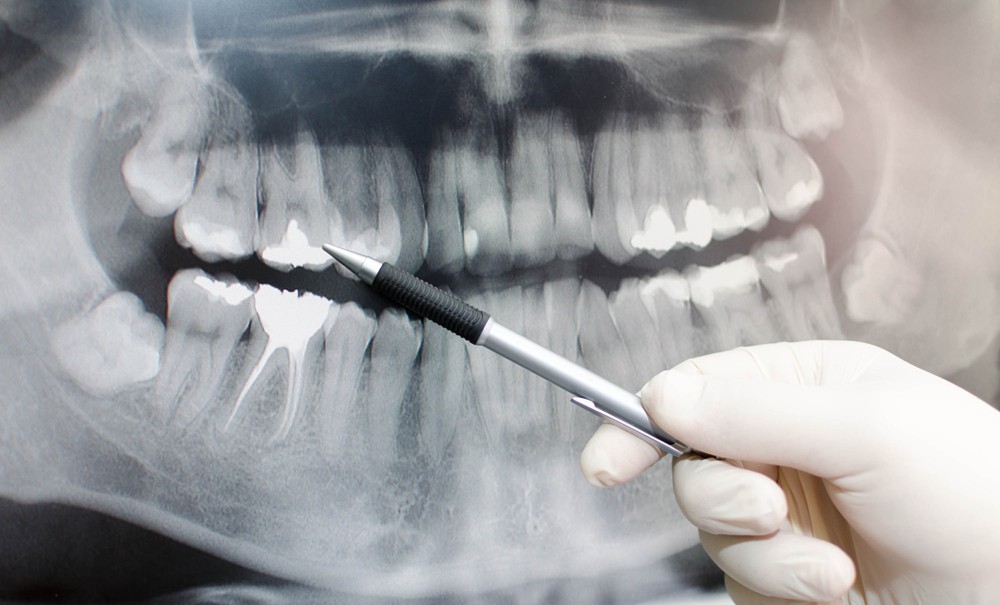

Imaginea dintr-o radiografie dentară este alb-negru, albul reprezentând orice este radio-opac (nu permite trecerea razelor X), iar negrul orice este radio-transparent (prin care trec razele X).

Medicul va determina exact prezenţa cariilor, infecţiilor, pungilor parodontale, fracturilor sau chisturilor, ca zone închise la culoare acolo unde nu ar trebui să fie.

Lucrările protetice, implanturile, plombele, se văd ca zone foarte albe, mai albe decât dinţii naturali.

- Panoramică – imagine de ansamblu a ambelor arcade